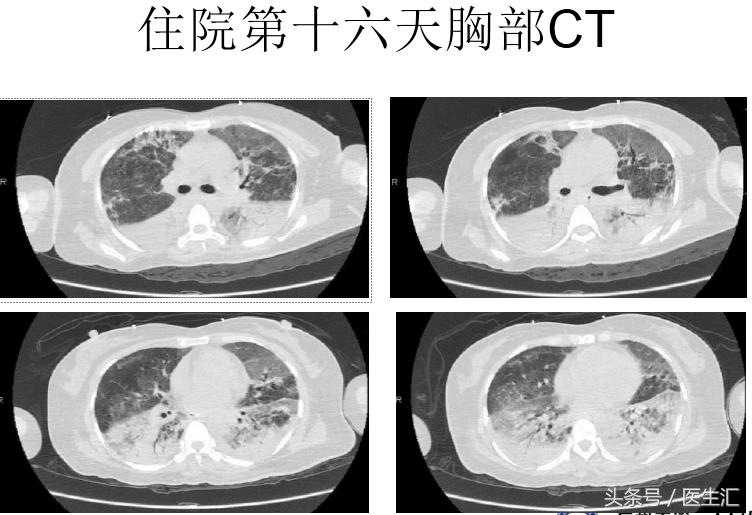

血常规:白细胞 28.49×10^9/L、红细胞 4.47×10^12/L、血红蛋白141.00g/L、血小板150.00×10^9/L,胆碱酯酶<200U/L,生化钾 3.27mmol/L、淀粉酶 315U/L、钠135.5mmol/L、氯 108.2mmol/L、肌酐 56.2μmol/L,脑利钠肽前体858.100pg/ml,凝血常规、凝血酶原时间 15.8s、活化部分凝血活酶时间47.5 s,D-二聚体 1185ug/L。胸片:拟右下肺野少许渗出灶。